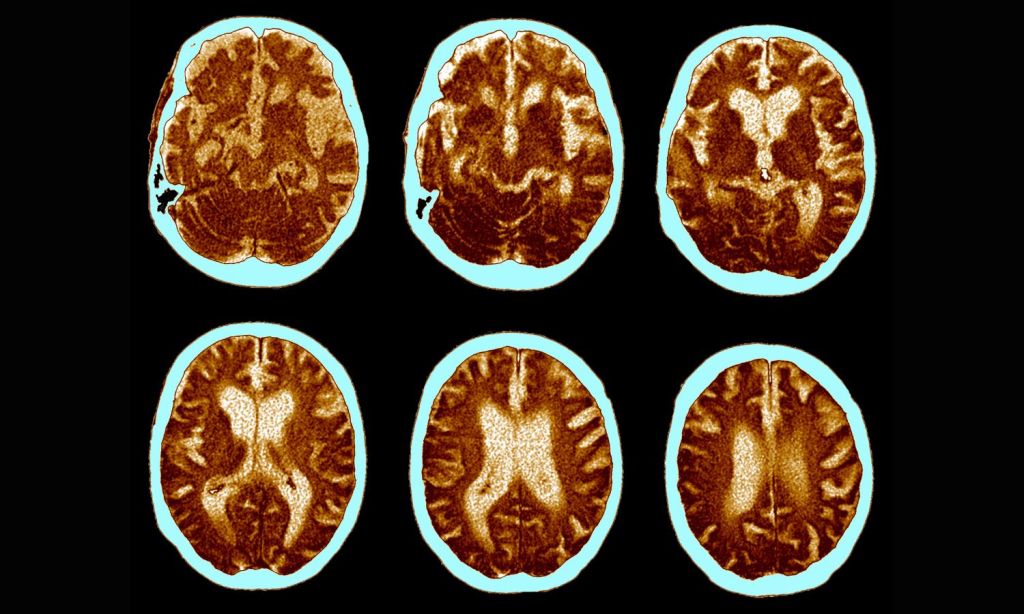

An image showing brains with Alzheimer's disease to illustrate an article on Alzheimer's breakthroughs